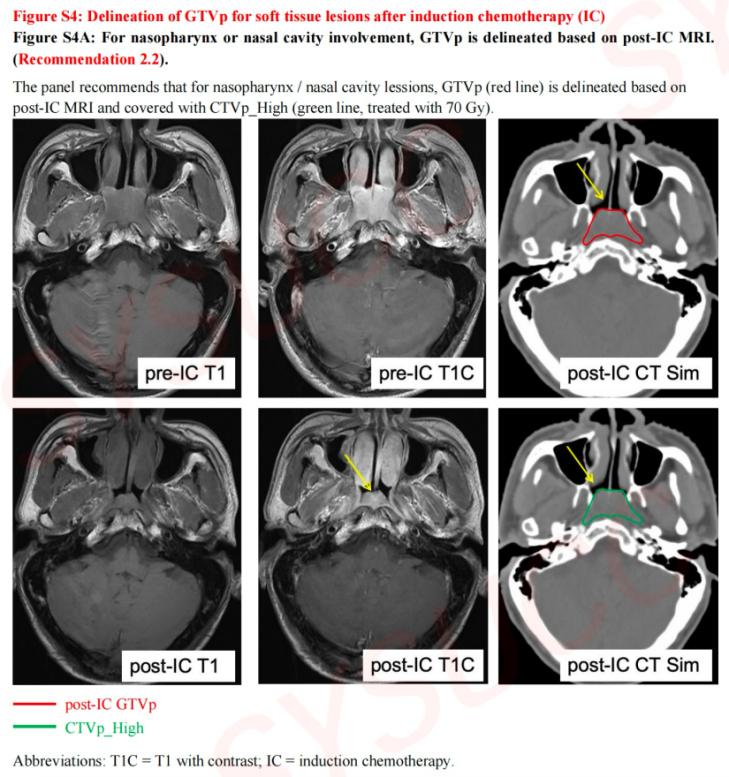

原發(fā)灶靶區(qū)勾畫圖譜示例